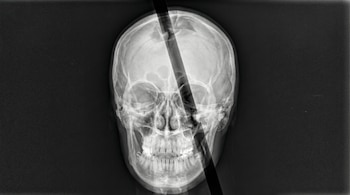

El 13 de septiembre de 1848, Gage trabajaba en la construcción del tendido ferroviario cuando una explosión accidental lanzó una barra de hierro —de casi un metro de largo, tres centímetros de diámetro y más de cinco kilogramos de peso— a través de su cabeza.

El proyectil penetró por su mejilla izquierda, cruzó detrás del ojo y salió por la parte superior del cráneo, cayendo a unos 30 metros de distancia.

Décadas después, la historia de Gage volvió a captar el interés de la ciencia gracias al avance de las tecnologías de imagen cerebral. Un equipo de la Universidad de California en Los Ángeles (UCLA), liderado por Jack Van Horn, utilizó resonancias magnéticas de más de 100 hombres jóvenes para reconstruir digitalmente el recorrido que habría seguido la barra de hierro dentro del cráneo.

Este modelo permitió estimar que el objeto atravesó alrededor del 4% de la corteza cerebral y afectó cerca del 11% de la materia blanca, la red de fibras que conecta distintas regiones del cerebro entre sí. Esa alteración en la conectividad interna se asemeja a la que se observa en trastornos neurológicos como algunas demencias.

“Si la barra hubiera ingresado con un ángulo apenas diferente, habría perforado alguna estructura vascular importante del cerebro y lo habría matado”, explicó Van Hor.